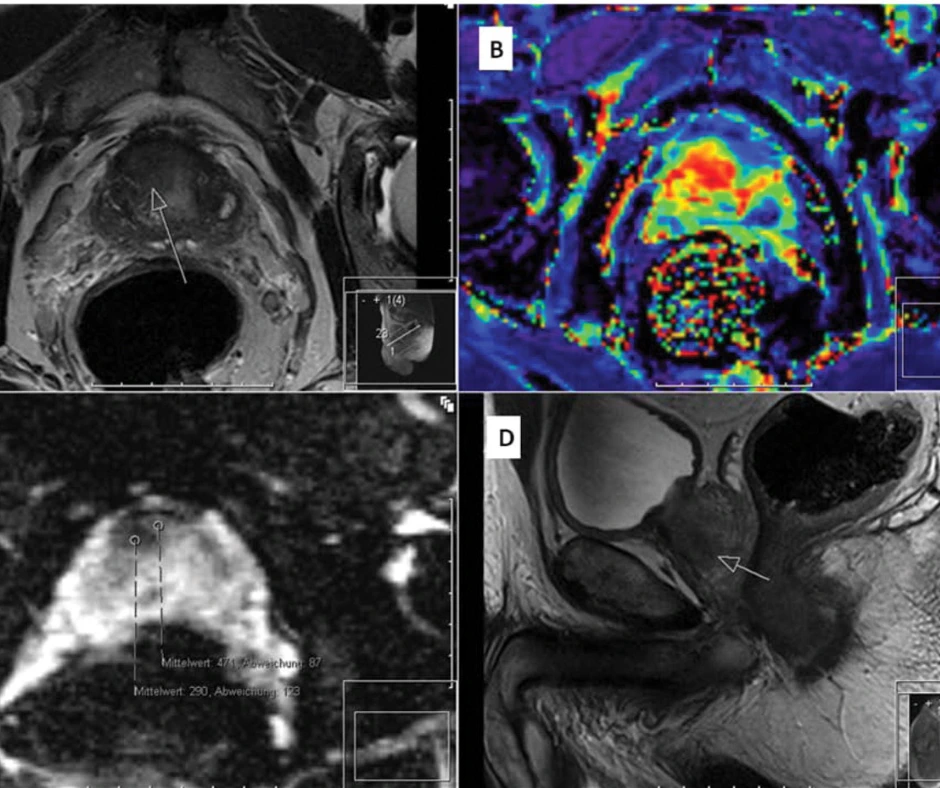

Завдяки багатошаровим зображенням лікар отримує можливість побачити структуру передміхурової залози з максимальною деталізацією. Особливо цінною є можливість оцінки тканин у трьох площинах, що дозволяє виявити пухлини на ранніх стадіях, простатит, кістозні утворення чи доброякісну гіперплазію.

«Сучасні апарати забезпечують високу якість зображень, а спеціальні програми дозволяють спеціалісту оцінити навіть метаболічну активність тканин. Це означає, що МРТ простати здатне не лише показати розмір і форму органа, але й визначити, чи є підозрілі зміни агресивними», — зазначає лікар-уролог клініки DocLife.

Найсерйозніша патологія, яку можна виявити за допомогою МРТ передміхурової залози — це рак простати. Дослідження дає змогу визначити локалізацію пухлини, оцінити її розміри, щільність, ступінь інвазії та поширеність за межі органа. Особливо важливим є мультипараметричне МРТ простати, яке допомагає урологу зрозуміти, наскільки агресивним є процес, і підібрати тактику лікування. Завдяки такій діагностиці вдається уникнути непотрібних біопсій та краще планувати хірургічні втручання чи променеву терапію.